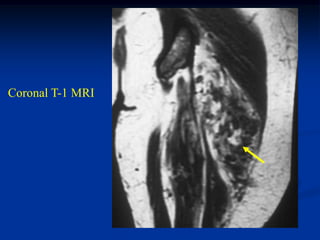

Case #1199

30 year male with

myxoid liposarcoma

posterior thigh

Sagittal T-1 MRI

Sagittal T-2 MRI

tumor

Axial T-1 MRI

Axial Gad contrast MRI

Coronal Gad

contrast MRI